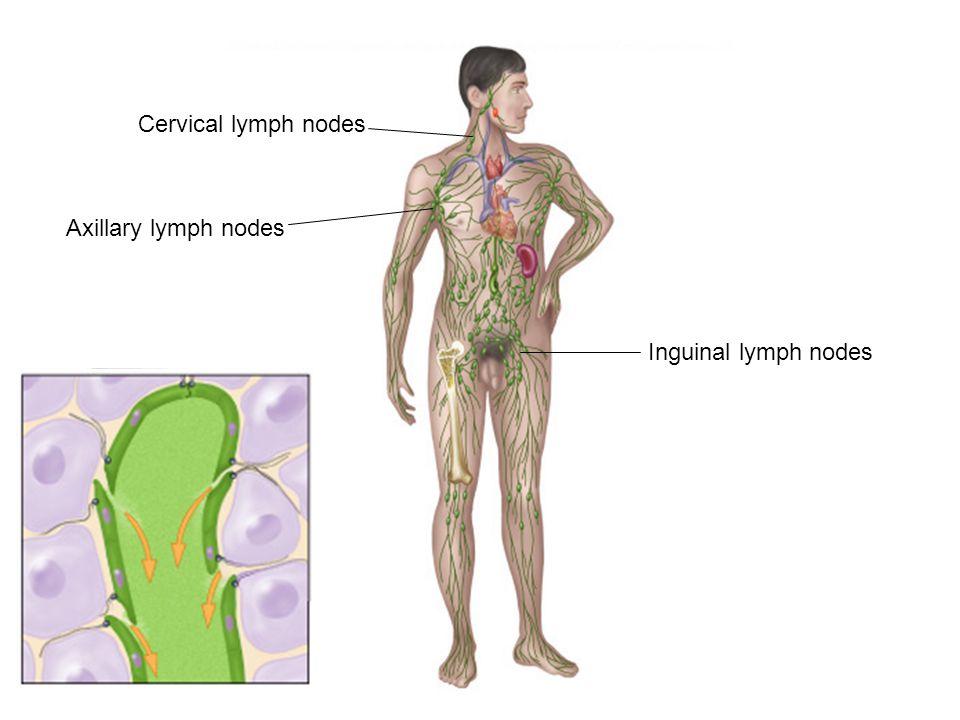

Изображения и схемы: как выглядит лимфа